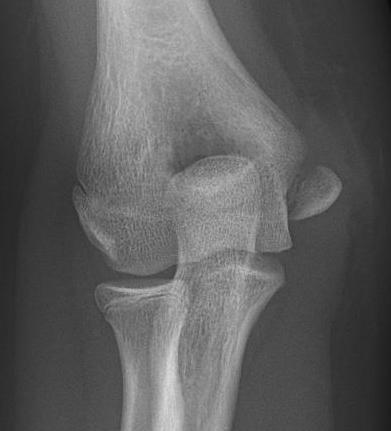

Displaced medial epicondyle fracture

Incarcerated medial epicondyle fracture

Clinical / Xray

- absent medial epicondyle on xray / compare to contralateral side

- non congruent joint reduction